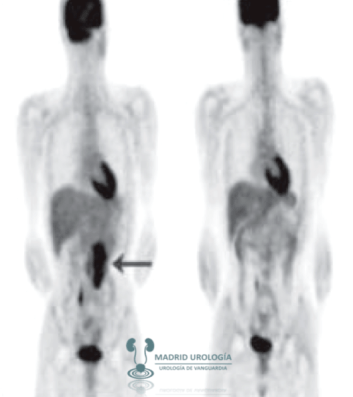

PET FLUORODEOXYGLUCOSE

§ No existe evidencia que soporte su uso en el estadiaje del CT.

§ Se recomienda en el seguimiento de pacientes con TCG Seminomatoso con masa residual tras 6 semanas de tratamiento con Quimioterapia para decidir Vigilancia Activa o Tratamiento Activo. (Re Estadiaje)

§ No existe recomendación para el Re Estadiaje en casos de TCG No Seminomatoso después de Quimioterapia.

| PET FDG ilustrativo. |